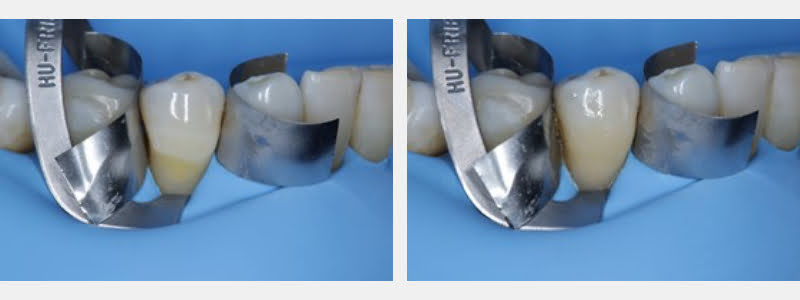

- Performed finishing and polishing of the restoration using polishing discs.

This technique aims to simplify absolute isolation using a rubber dam and direct restoration using a modified 212 clamp on a patient who had two adjacent teeth with cervical carious lesions and NCCLs, along with fine or thick periodontal phenotypes with exposed root surfaces.

By using a modified 212 clamp alternately between the teeth that will be restored, the time the procedure takes is optimized and the risk of periodontal tissue damage is reduced. Other advantages of this technique include:

- Protects the patient’s underlying soft tissue.

- Takes less clinical time because more than one adjacent tooth can be restored at a time.

- Decreases the risk of post-operative gingival recession when using a modified clamp that has proper adaptation to the cervical morphology.

- Allows the clinician to create a proper emergence profile for the restoration because an absolute isolation technique treats the more extensive mesial-distal area of the teeth, and the field of view is better, translating into a proper adaptation of the restoration.

- It affords the clinician a better polish and finish of the restoration because a modified 212 clamp widens the space between the clamp’s jaws and the arch, permitting the use of a contrangle to perform these procedures.